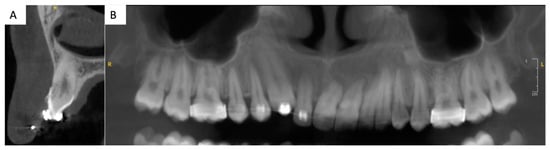

Figure 2. Three-dimensional imaging, CBCT (cone beam computed tomography): (A): sagittal section of tooth 13. Thin buccal and palatal cortical bone plates and proximity of the apex of 13 with the right nasal cavity can be noted. (B) Two-dimensional reconstruction of the upper jaw. Important root resorptions of the central maxillary incisors can be noted. A root resorption of the lateral incisor is also present.

Upon clinical and radiological examination (Figure 1, Figure 2 and Figure 3), the patient exhibited a harmonious face; a reduced lower facial height; an impacted, ankylosed, and severely infra-occluded right maxillary canine; an upper dental midline deviated 2 mm to the right; a skeletal class II associated with a class II division 1 malocclusion; and an iatrogenic clockwise cant of the maxillary occlusal plane with simultaneous adaptation of the mandibular arch. Several root resorptions were observed, with all maxillary incisors exhibiting signs of this phenomenon. However, the central incisors appeared to have undergone a particularly pronounced degree of root resorption. The clinical diagnosis of ankylosis of # 13 (upper left canine, World Dental Federation notation) was confirmed by the observation of a cant of the occlusal plane, a metallic sound after axial percussion, and a lack of mobility of the canine. A radiographic examination (Figure 2) revealed that the root was centred within the alveolar process. An external resorption with bone replacement was evident in the cervical region on the buccal side of the canine, indicative of tooth ankylosis. In contrast to the thicker palatal cortical bone, the buccal cortical plate was less than one millimetre thick.

A multidisciplinary consultation was convened between the departments of dentofacial orthopaedics, oral surgery, periodontics, and prosthodontics, with the objective of developing an optimal treatment that would honour the patient’s desire for an aesthetic restoration of the smile within a limited timeframe. In consideration of the functional and aesthetic requirements, as well as considering the residual vertical alveolar growth, it was determined that a fixed tooth-supported prosthetic rehabilitation of tooth # 13 was the optimal course of action, given the pre-existing multiple root resorptions [7] (Figure 2). This objective could be achieved through the correction of the occlusal plane cant and partial extraction of the upper right canine, in conjunction with a soft tissue surgery in the newly edentulous area.